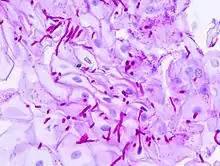

Diagnosis of a yeast infection is confirmed either via microscopic examination or culturing. For identification by light microscopy, a scraping or swab of the affected area is placed on a microscope slide. A single drop of 10% potassium hydroxide (KOH) solution is then added to the specimen. The KOH dissolves the skin cells, but leaves the Candida cells intact, permitting visualization of pseudohyphae and budding yeast cells typical of many Candida species.